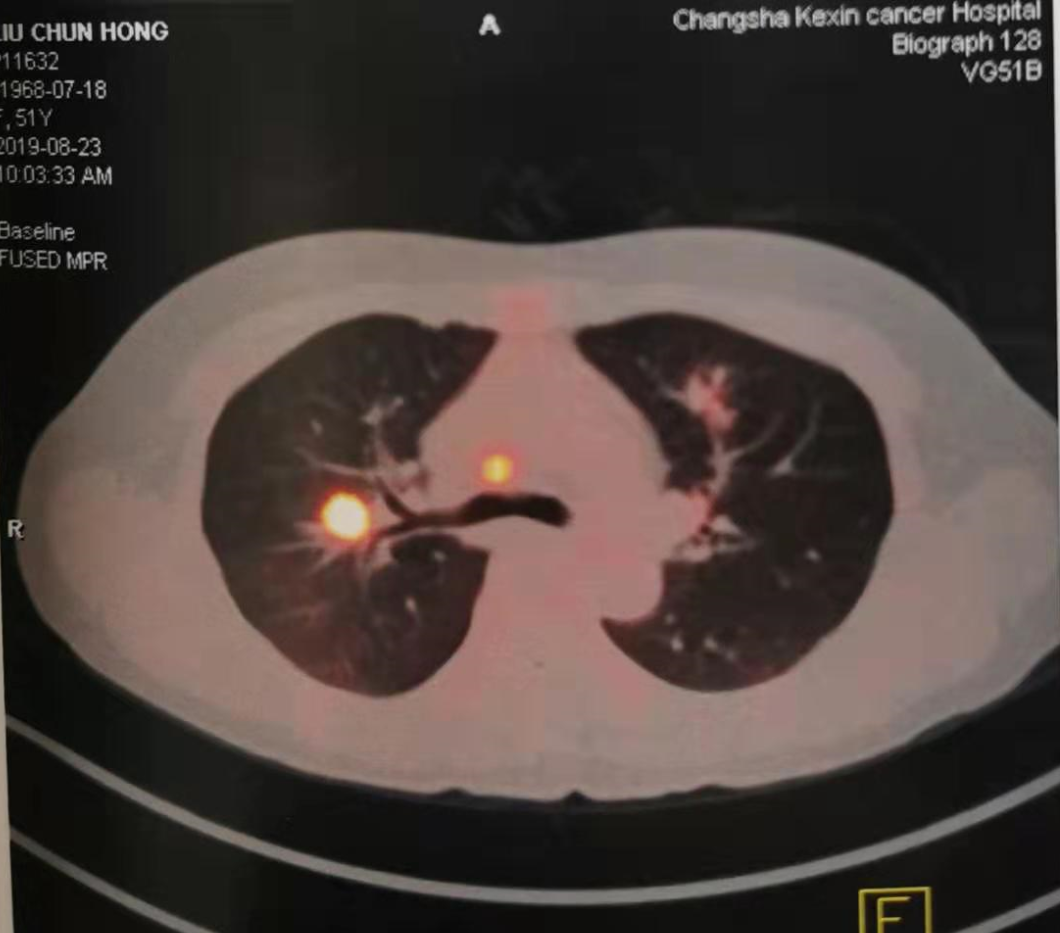

2019年8月(51岁),来院检测CT示肺部阴影,PET-CT示高代谢病灶。行超声支纤镜活检示:低分化鳞癌。

图2:2019年8月23日CT及PET-CT结果

PET-CT: 2019/8/23

(靶向治疗前)

PET-CT: 2019/12/23

(靶向治疗3个月)